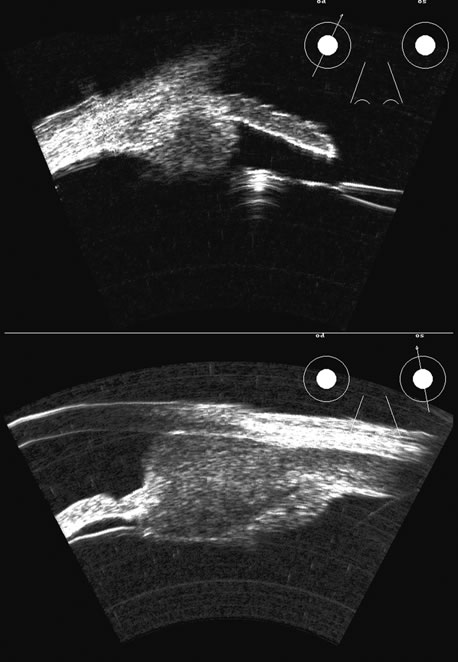

Hypotony is easily diagnosed by direct measurement of intraocular pressure, but the underlying cause is difficult to evaluate.11 High-frequency ultrasound scans can easily reveal separation of the ciliary body and the sclera. This allows different forms of hypotony to be determined—for example: tractional with membrane attached; primary as idiopathic, often inflammatory or hemorrhagic; and dehiscence secondary to iridodialysis or scleral perforation (Fig. 6).

Fig. 6. Hypotony of the eye generally is easily diagnosed by a separation of the ciliary body from the sclera. We have noted several types of such separation, such as tractional, primary (idiopathic), and dehiscence secondary to iridodialysis or scleral perforation, as in filtration procedures. In our series, greater than two clock hours of separation is typical of hypotony. The lower figure shows a concomitant thickening of the retina-choroid complex, also seen in hypotony (arrows). Long-standing hypotony typically has a shortened globe and possible retinal or choroidal separation.